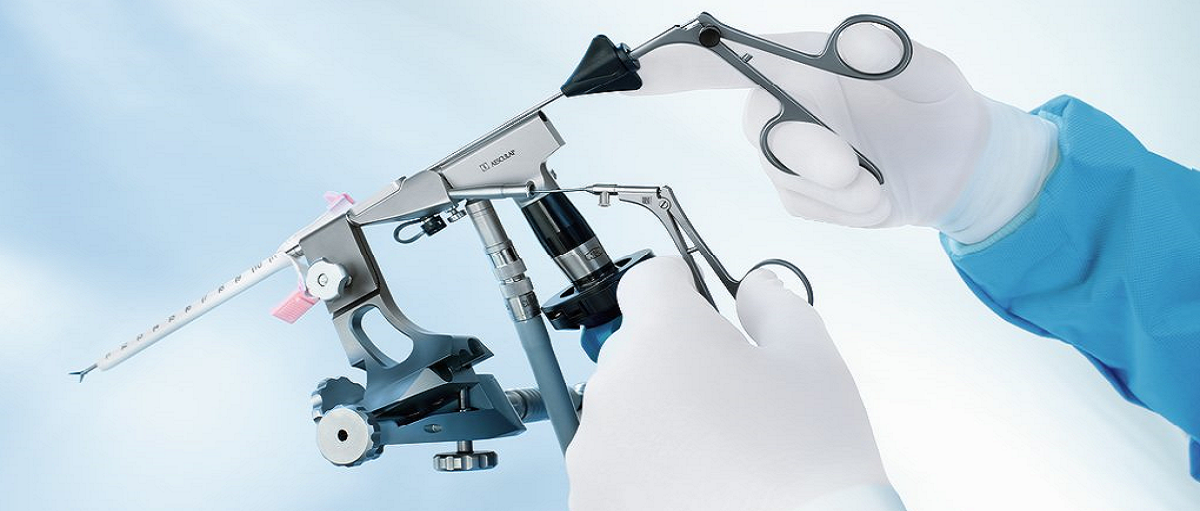

The precise planning and performance of neurosurgical procedures on the brain, spine, spinal cord and peripheral nerves require the operating surgeon‘s utmost concentration. Every decision has consequences and must be made with great care. Every step carries risks and must be approached with caution. Every surgery is strongly connected with hopes and fears of the patient and their relatives in anticipation of a full recovery.

We understand the gravity of the situation and consider it our duty, as a partner of neurosurgeons, to support them with precise, reliable and high-quality solutions. Our products and services are designed to make their demanding working life easier, allowing them to turn their full attention to saving people, prolonging lives and improving quality of life.